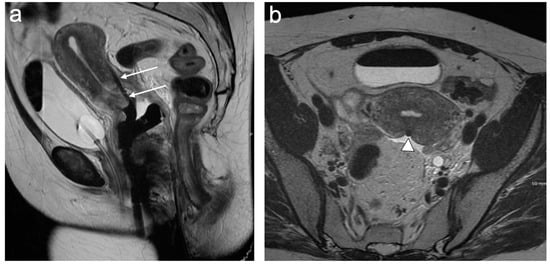

6. FIGO Stage III

7. FIGO Stage IV